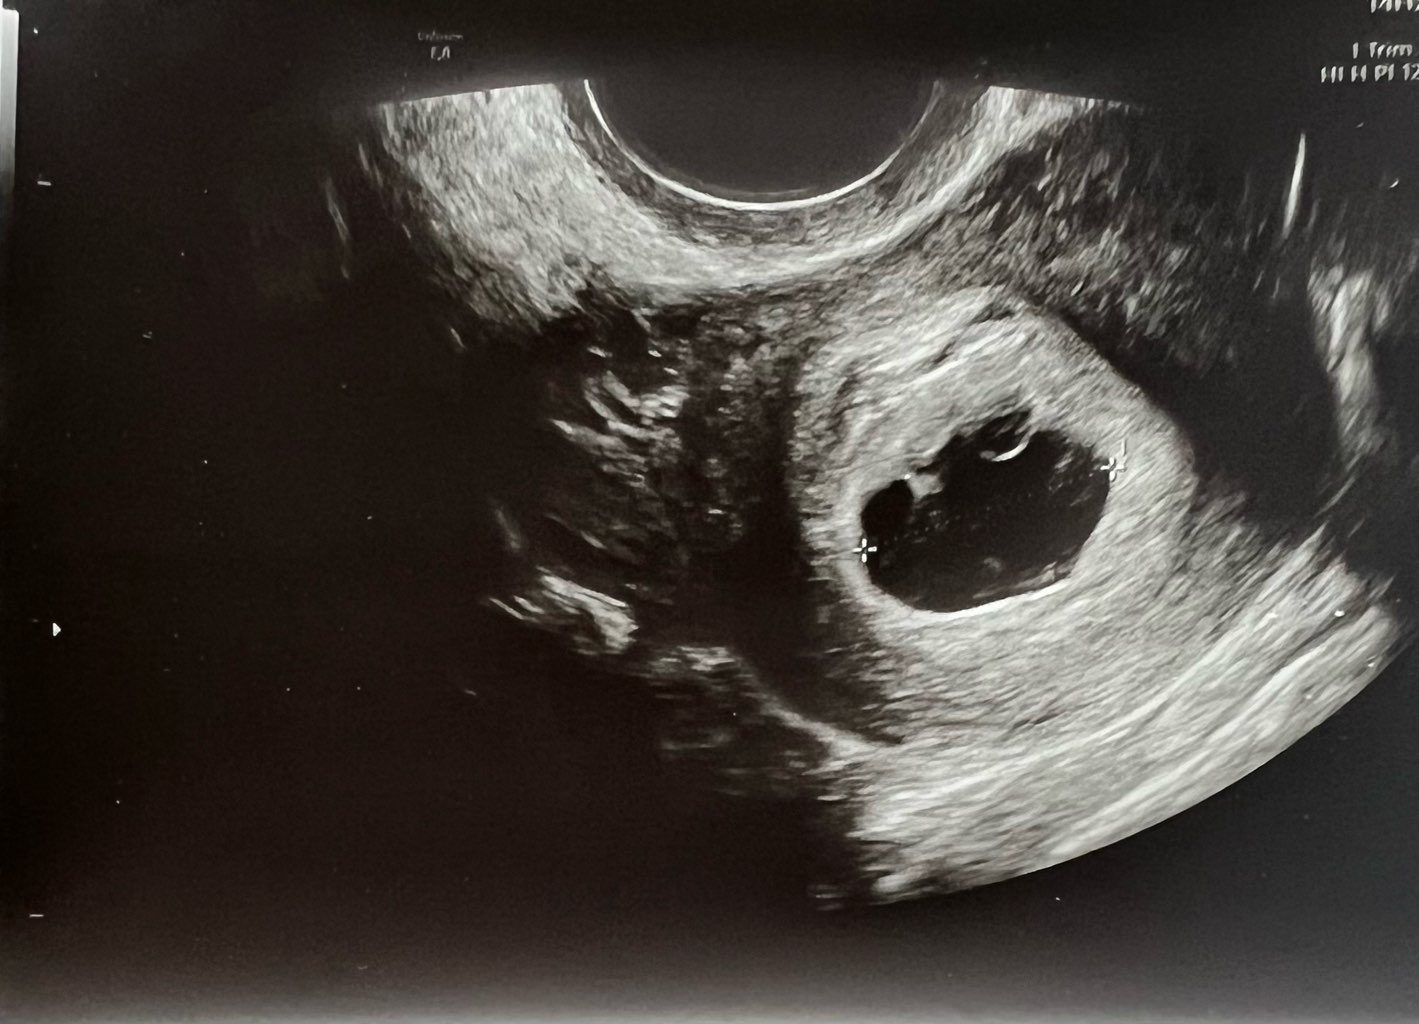

U mnie tak wyglada pęcherzyk ciążowy. Dwóch ginekologów zwróciło na to uwagę, że jest nieregularny kształt. W piątek byłam w szpitalu, byłam wtedy 6t6d i doktor zauważyła zarodek 2mm i wątpliwe tętno zarodka.@PepkaS a masz może zdjęcie z USG? Co to znaczy że nieregularny kształt? Bo mój w pierwszej ciąży i teraz jest w kształcie takiej fasolki.

Jutro idę do gin, więc zajrzy tam i zobaczymy, ale w piątek też mam wizytę w szpitalu. Ogólnie dostałam sygnał, żebym się nie nastawiała, może być tak, że zarodek się nie rozwinie

Czytałam tu na forum, że kobiety miały takie nieregularne pecherzyki i niektóre z nich donosiły ciąże i dzieciaczki są zdrowe. A tym, którym się nie udało nastąpiło poronienie.

Mój pęcherzyk też był taki nieregularny lekarz mówił że jest za mały, zarodek z sercem już był. I echo takie sobie, też mówił że częstotliwość bicia jako tako... Ten mój pęcherzyk przypominał jakby PolskeU mnie tak wyglada pęcherzyk ciążowy. Dwóch ginekologów zwróciło na to uwagę, że jest nieregularny kształt. W piątek byłam w szpitalu, byłam wtedy 6t6d i doktor zauważyła zarodek 2mm i wątpliwe tętno zarodka.

Jutro idę do gin, więc zajrzy tam i zobaczymy, ale w piątek też mam wizytę w szpitalu. Ogólnie dostałam sygnał, żebym się nie nastawiała, może być tak, że zarodek się nie rozwiniei nastąpi poronienie. Dlatego chodzę jak na tykającej bombie.

Za to pęcherzyk mojej szwagierki która też jest teraz w ciazy i różni nas tydzien, był w kształcie jakby plemnika . Taki podłużny dziwny. Też jest wszystko okej

Wiadomo, lekarze sie na tym znają ale czasem jakieś błache rzeczy wyolbrzymiają trochę, może żeby pacjentki we wczesnym etapie mialy troszkę dystans do ciazy

Nie wiem. Mój mnie mega nastraszył i pisałam to też tu na forum że się martwię...